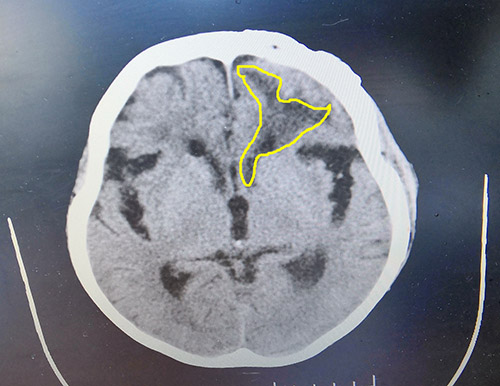

▲患者脑出血病灶区域

神经外科6B病区主任详细了解了王老太受伤、手术治疗等情况,并为王老太完善相关检查。头颅CT显示,左侧额叶见不规则斑片状低密度影,右侧额叶小斑片状低密度影;胸部CT显示两肺炎症,两侧胸腔少量积液;患者头部可见长约15cm陈旧性手术切口,局部切口创面可见一约3cm×3cm大小破溃,表面可见少许白色分泌物;呼吸音粗,双肺可闻及湿罗音,痰多且粘稠。